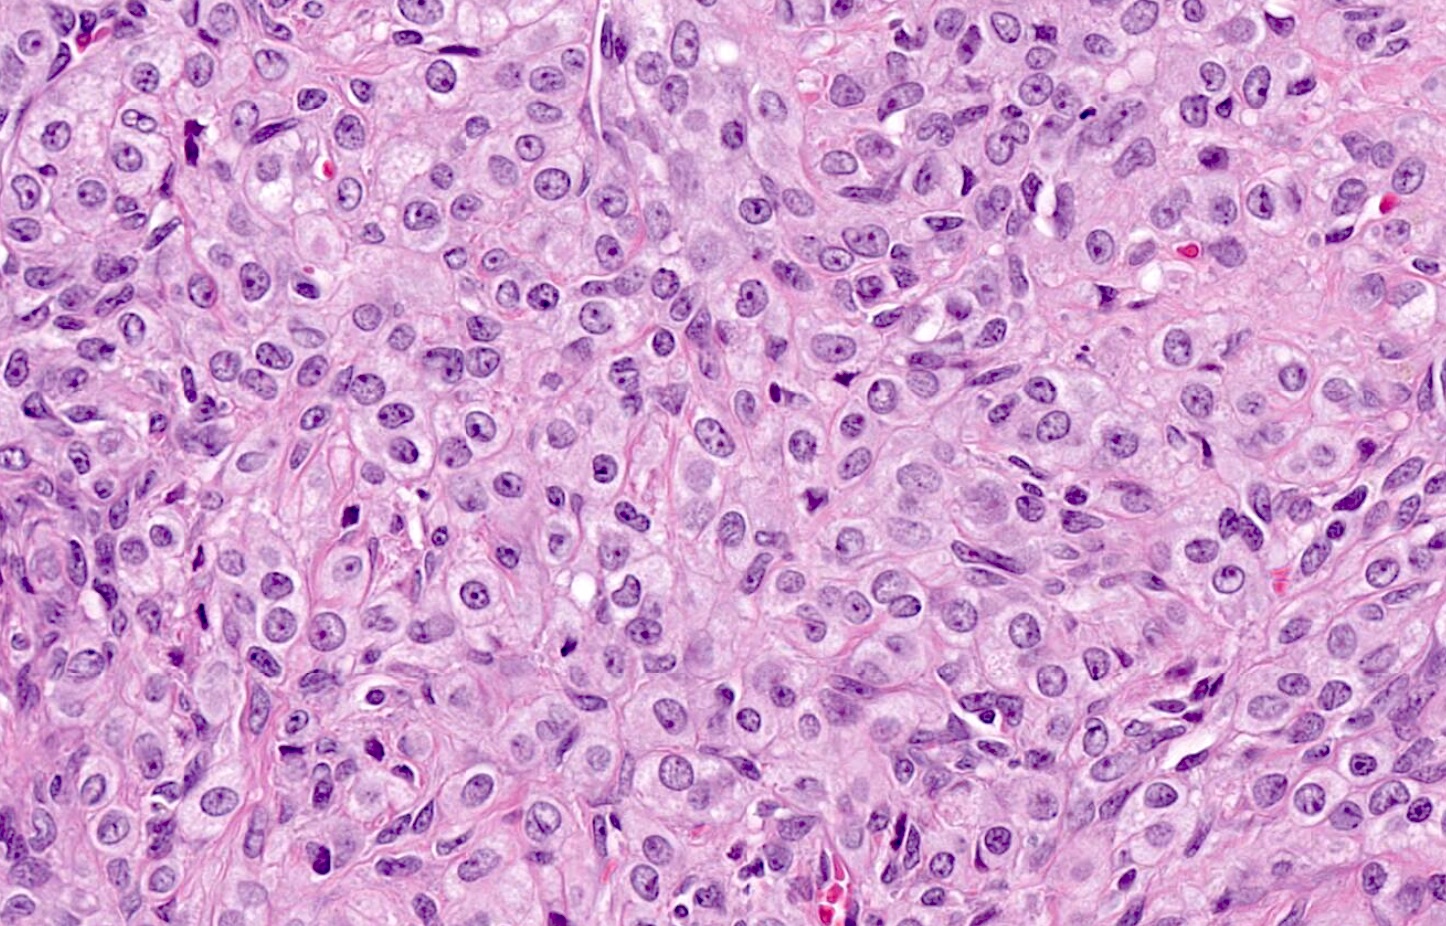

Microscopic (histologic) description

- Predominant population of cells showing ovoid to round nuclei and pale gray cytoplasm, which can be abundant

- Minor component of the tumor may have spindled nuclei, reflecting overlap between fibroma and thecoma

- Indistinct cell membranes impart a syncytial appearance

- Diffuse or nodular growth pattern

- Absent or minimal nuclear atypia

- Mitotic rate usually < 5/10 high power fields

- Hyaline plaques

- Cytoplasmic lipid vacuoles may be present but are not essential

- May show aggregates of cells with brightly eosinophilic cytoplasm (lutein cells)

- Calcification is more common in young patients (Int J Gynecol Pathol 1988;7:343)

- Uncommon features include keloid-like sclerosis, nuclear grooves, bizarre nuclear atypia (Am J Surg Pathol 2014;38:1023)

- Rarely contains a minor component of sex cord elements (Int J Gynecol Pathol 1983;2:227)

- Malignant thecoma: very rare, diagnosis requires diffuse moderate to severe nuclear atypia and high mitotic rate (> 4/10 high power fields) (Am J Surg Pathol 2011;35:e15)

Microscopic (histologic) images

Contributed by Victoria Collins, M.D., Tamara Kalir, M.D., Ph.D., AFIP and @SeoparjooAzmel on Twitter